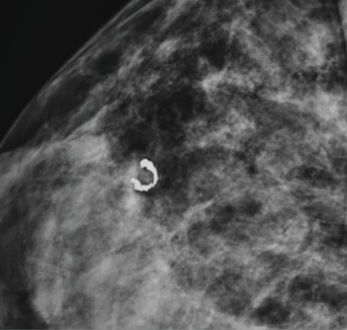

nodulo espiculado

calcificações pleomórficas

Nodulo com margens nao circunscritas, qual a classificação do BIRADS?

4